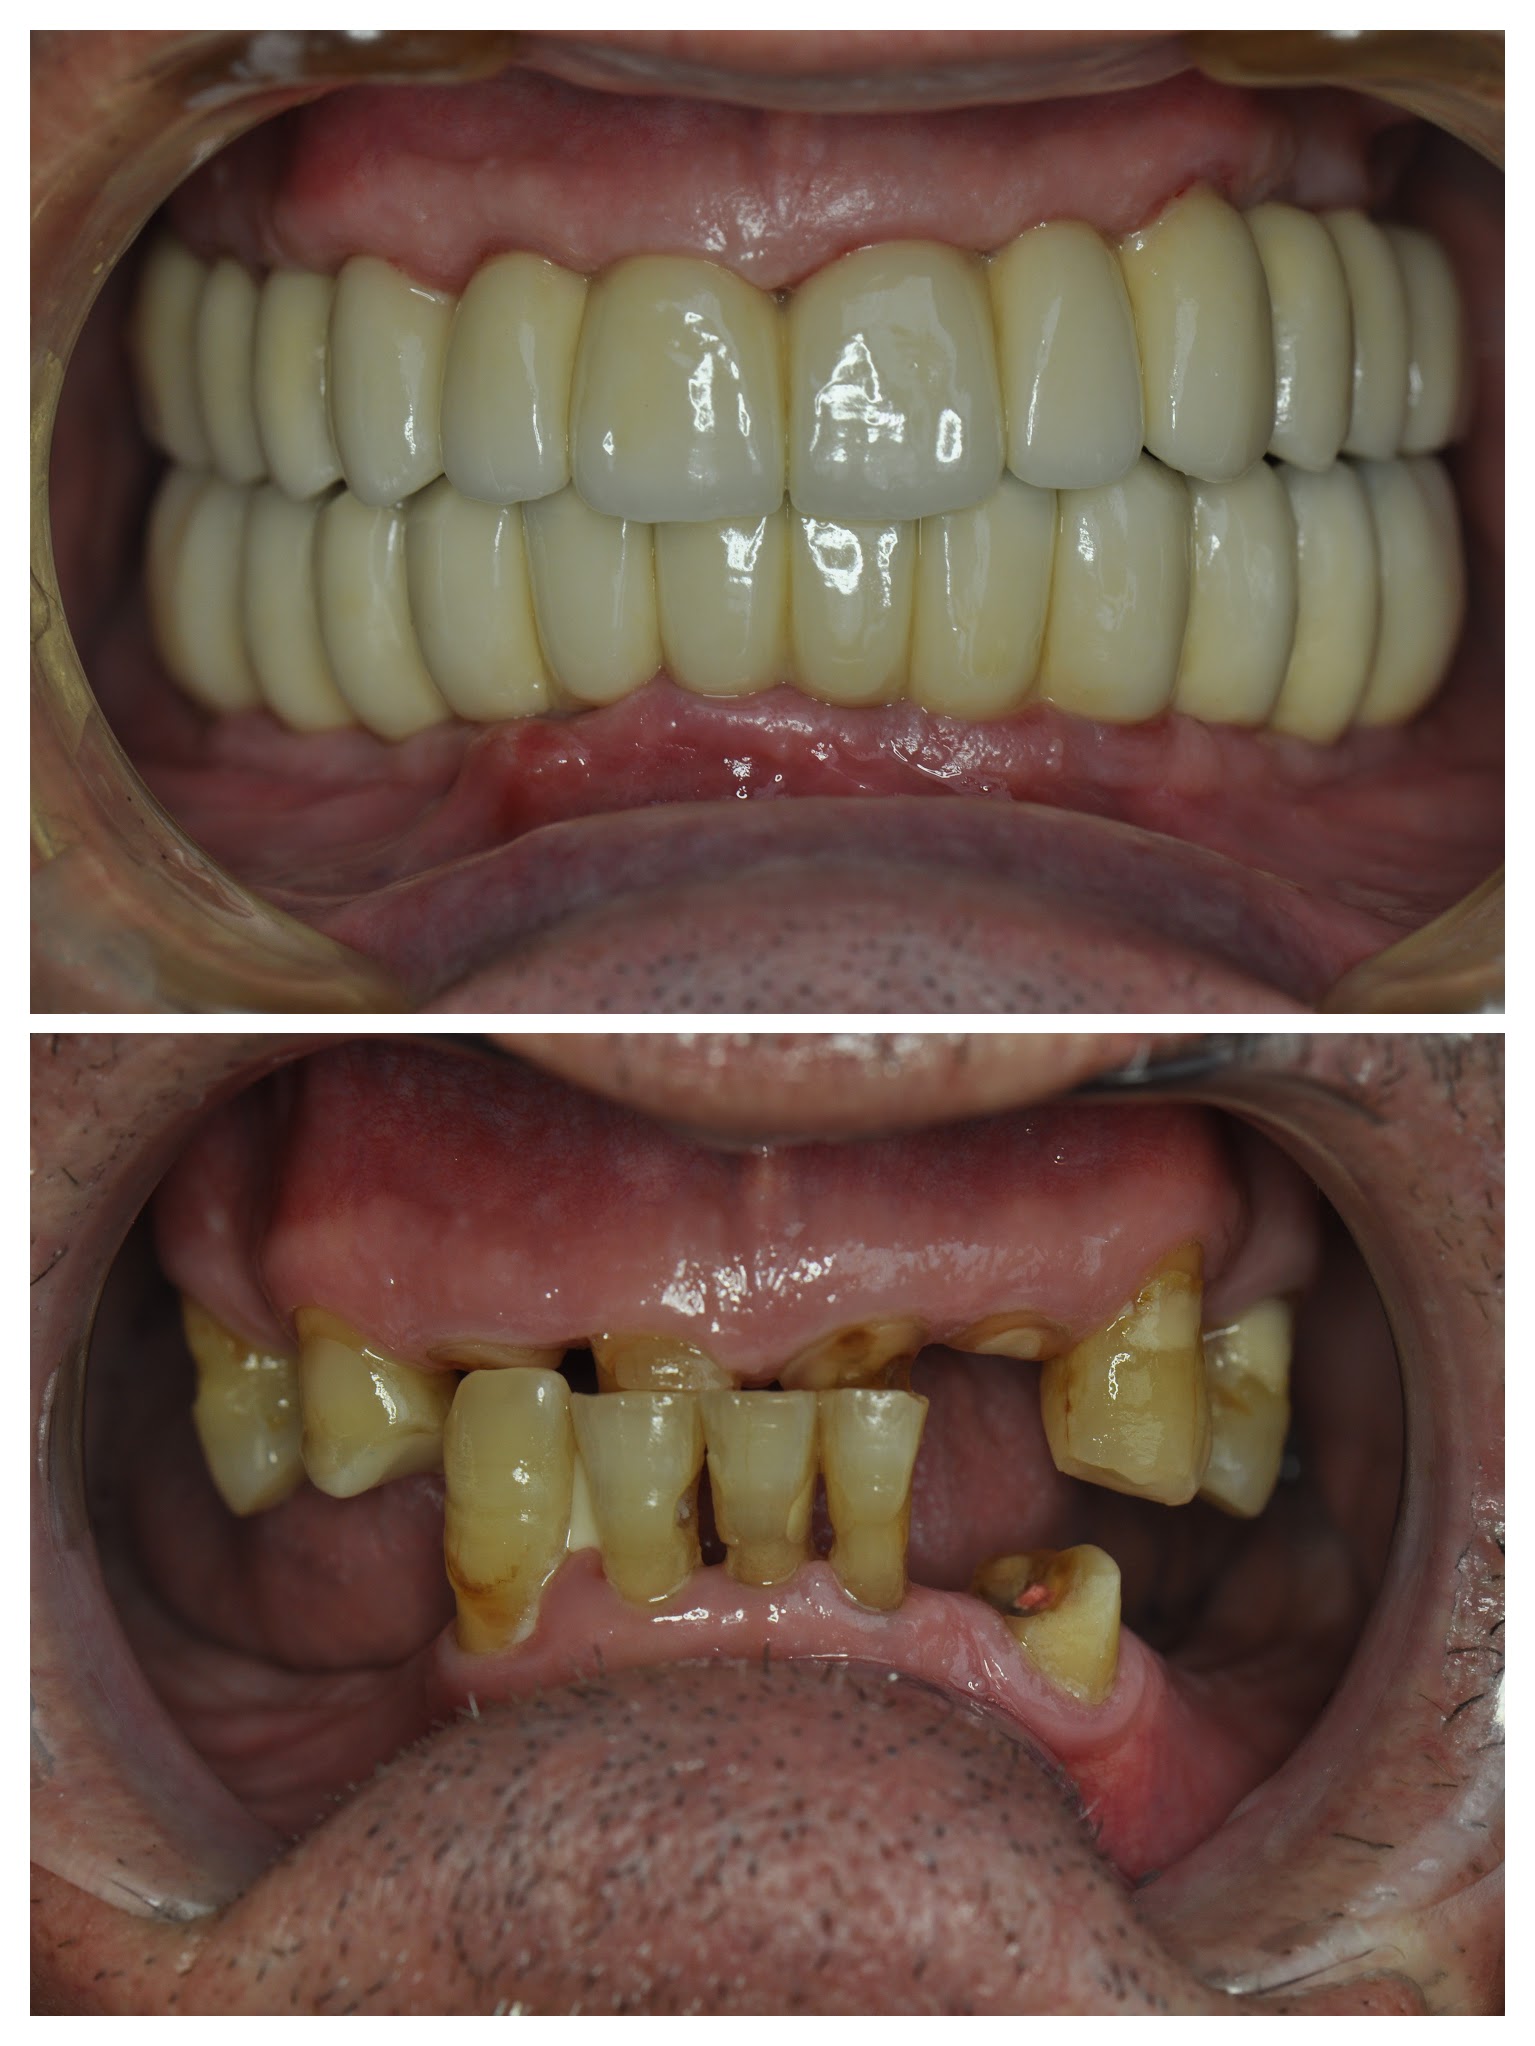

Aggi was one of our many “all on 5” and “all on 6” dental implant cases for both the upper and lower jaw that began in the second half of 2016 and completed in the 1st half of 2017.

As you can see from the photographs and x-rays, this was a relatively complicated case due to the lack of bone available (hence more implants being used). This is often typical of patients who have smoked in the past, had poor nutrition, suffered from serious illnesses, or simply a factor of aging.

Having said that, however, we have yet to have a case (and we’ve done over 3000 now) where we have not been able to throw out the idea of false teeth, and replace them with a full set of permanent crowns using dental implants.